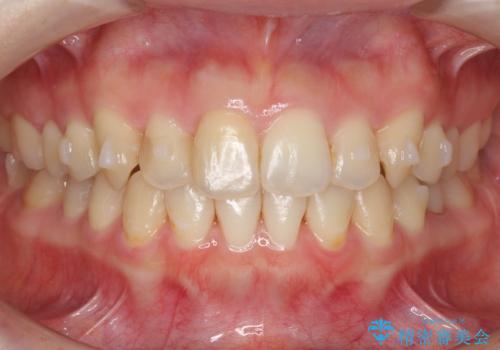

犬歯のねじれ 上の歯が引っ込んでいる

- 前歯の並びを気にして来院。

インビザラインで、上の前歯をやすり掛けして並べました。